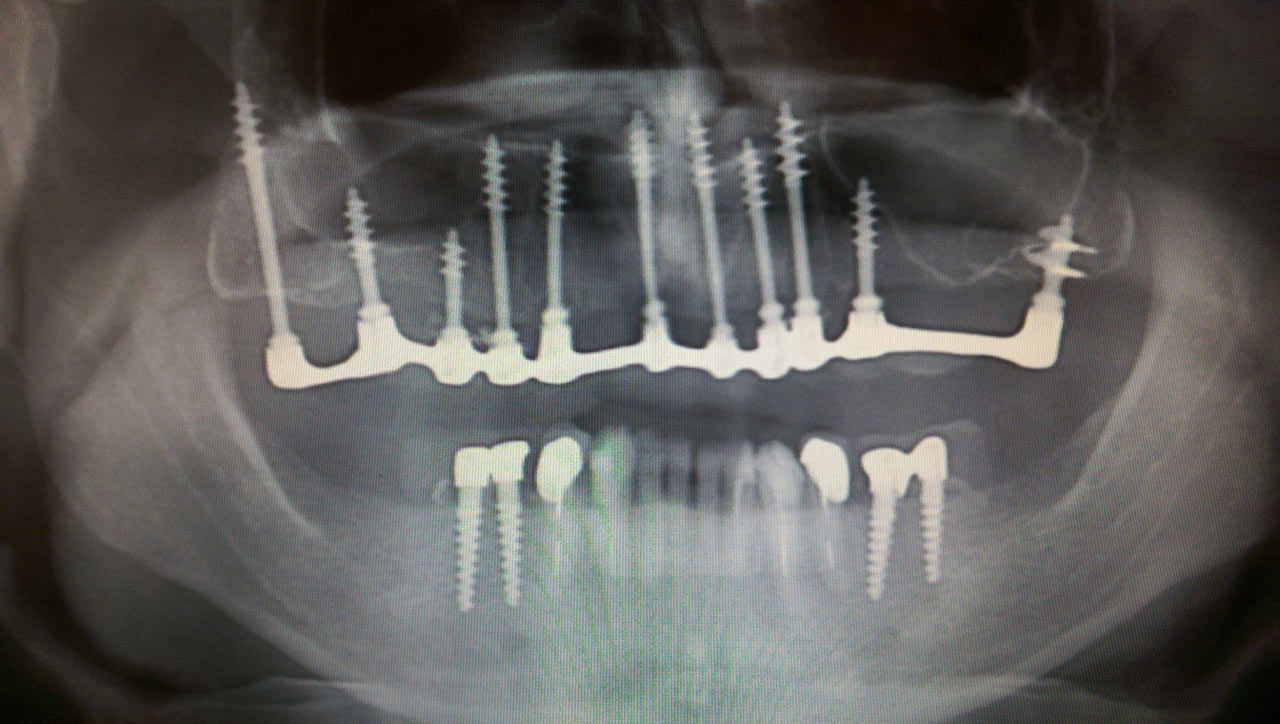

Teljes fogatlanság helyreállítása 2 nap alatt

Teljes fogatlanság helyreállítása 2 nap alatt azonnal terhelhető svájci IHDE implantátumokkal és PMMA műanyag hidakkal. Intraorális szkennerrel vettünk lenyomatot az implantáció után, és erre a digitális mintára készítette el a fogtechnika a hidak digitális tervezését, majd faragta ki műanyagból. Ezt a gyors munkát az azonnal terhelhető implantátumok és a digitális lenyomat, tervezés segítségével tudtuk megcsinálni mindössze 2 nap alatt. Dr. Kelemen Péter és a Symbion Fogtechnika munkája.